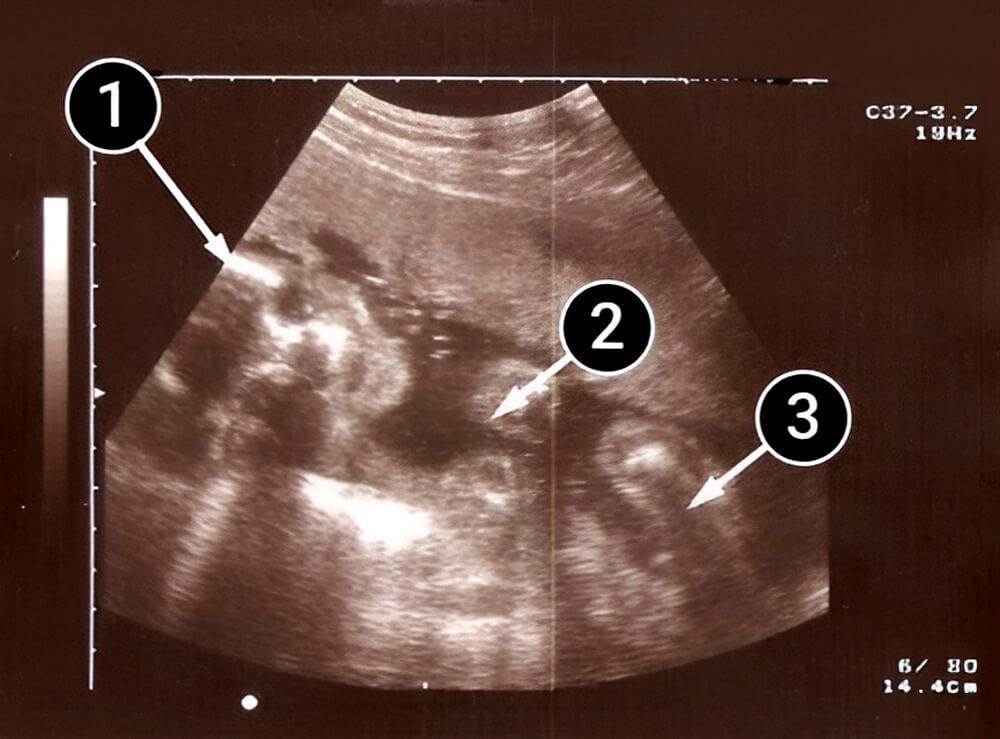

Lo que podemos ver en un ultrasonido

En la imagen, el bebé está acostado de lado, de frente a la pantalla. La cabeza, los brazos y las piernas son claramente visibles.